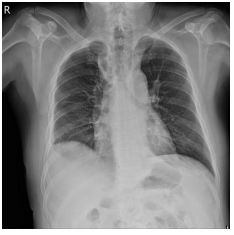

1. A 39-year-old man had this chest X-ray on his health exam. No any clinical symptoms.